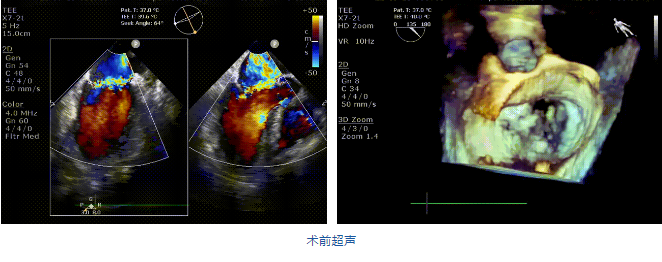

接受治療的是一例二尖瓣重度反流的患者,主訴“突發間歇性胸悶,氣急6天”。術前超聲提示:1.二尖瓣脫垂伴重度關閉不全(瞬時量30ml);2.左心、右房增大(左房容積110ml,左室容積129ml,右房容積55ml);3.左室收縮功能正常?;颊咴诔浞謽藴驶幬镏委熀螅℅DMT)仍然癥狀明顯,韓林教授及其團隊唐楊烽教授,以及心超科的周廣為醫生決定使用我國創新器械JensClip為患者進行二尖瓣緣對緣修復手術。

在阜外醫院潘湘斌教授團隊的支持下,手術經股靜脈-房間隔入路,采用全身麻醉插管,在TEE和DSA引導下完成房間隔穿刺。置入JensClip瓣膜夾系統后,在左房調整瓣膜夾的位置和軸向,后進入左室,在TEE引導下捕捉二尖瓣前后瓣葉,并關閉瓣膜夾。經TEE反復確認手術效果后最終鎖定并釋放瓣膜夾。術后即刻超聲顯示瓣膜夾位置穩定,功能良好,二尖瓣反流由術前4+減少至微量,手術圓滿成功。